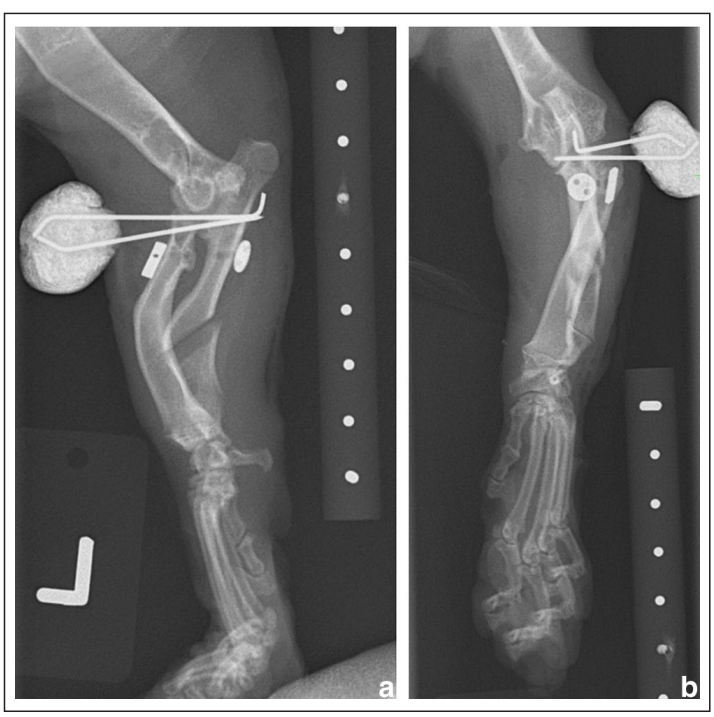

↑ 左(ac)和右(bd)前肢的正侧位和头尾位X光片。双侧桡骨头半脱位,桡骨弯曲,尺骨短小,远端尺骨生长板过早闭合,尺骨呈内翻畸形。这些变化与软骨发育不良、双侧肢体弯曲畸形、肘关节发育不良以及随后的发育型I桡骨头半脱位以及肱尺关节半脱位相符合,左侧稍显严重。

↑ 左前肢术后即刻的 (a) 正侧位和 (b) 头尾位X光片。桡骨头已复位至更接近解剖位置。尺骨截骨处存在间隙,与尺骨的释放和动态牵张相符合。桡骨和尺骨之间有一个透光的骨隧道,其中放置了桡尺骨切换针和按钮,以及两根发散的克氏针,它们以骨间位置穿过桡骨和尺骨,并从近端前臂的头侧表面穿出。